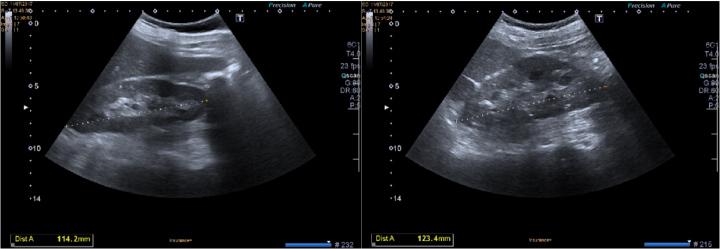

Pseudoxanthoma elasticum (PXE) is a rare genetic disorder characterized by calcification of elastic fibres, skin lesions, fundus lesions and systemic vascular complications. PXE affects approximately 1 in 160,000 people, typically appearing as a formation of yellow papules containing abnormally calcified elastic fibres. The renal involvement of PXE has been reported. Several factors are known to promote soft tissue and accelerated arterial calcification in chronic kidney disease, including systemic inflammation, altered calcium and phosphate homeostasis, hypertension and a deficiency of endogenous calcification inhibitors. Given the impact of this disease, nephrologists may seek additional supportive features to improve and avoid the risk of complications. Moreover, PXE per se represents an interesting model to evaluate vascular disease in the early stages of renal disease.